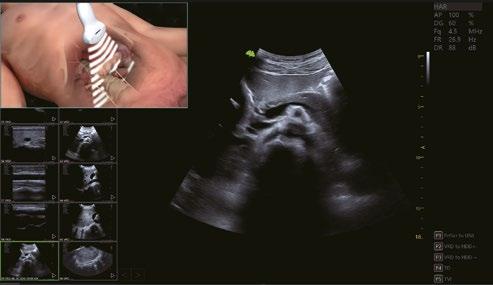

Verbesserte Nadelvisualisierung, um die Genauigkeit bei Biopsien oder Eingriffen zu verbessern.

Nadelverbesserung AUS

Nadelverbesserung AN